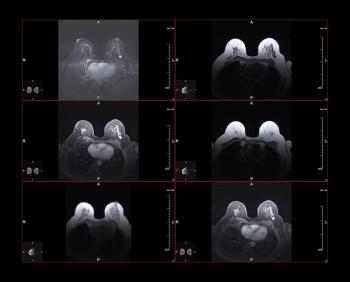

For HER2-positive breast cancer patients with radiologic complete response on breast MRI after neoadjuvant chemotherapy (NAC), the absence of calcifications was associated with over a 13 percent higher positive predictive value (PPV) for pathologic complete response (pCR).